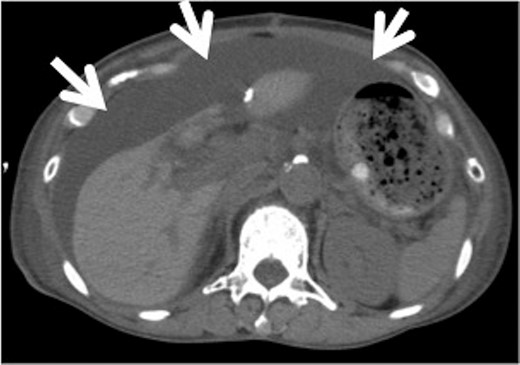

We considered it unlikely that the intrathoracic segment of the thoracic duct was damaged during the previous surgery because there was no documentation of intraoperative diaphragmatic injury, which can often occur in oesophageal cancer operations. We believed the chylothorax occurred regardless of the abdominal surgery. We planned to examine the thoracic cavity and ligate the thoracic duct during video-assisted thoracoscopic surgery. Intraoperatively, we detected a small fistula on the right hemidiaphragm and closed the fistula with partial resection of the diaphragm (Fig. 2A–C). We also ligated the thoracic duct as originally planned. The fistula appeared to be fibrotic; however, no other pathological abnormality was observed in the excised diaphragmatic tissue. Postoperatively, the patient resumed oral intake. The pleural effusion did not increase in volume and the pleural fluid triglyceride level was within normal limits (12 mg/dL). Nine days later, she reported a sensation of abdominal distension. An abdominal computed tomography revealed large ascites (Fig. 3). Abdominocentesis was performed, and the triglyceride level in the ascites was elevated (124 mg/dL). She was diagnosed with chylous ascites. By maintaining the abdominal cavity drainage, discontinuing oral intake and continuing octreotide administration for 3 weeks, the chylous ascites gradually improved.

Abdominal computed tomography (CT) after thoracic surgery. Abdominal CT after thoracic surgery shows sub-massive ascites (arrows).